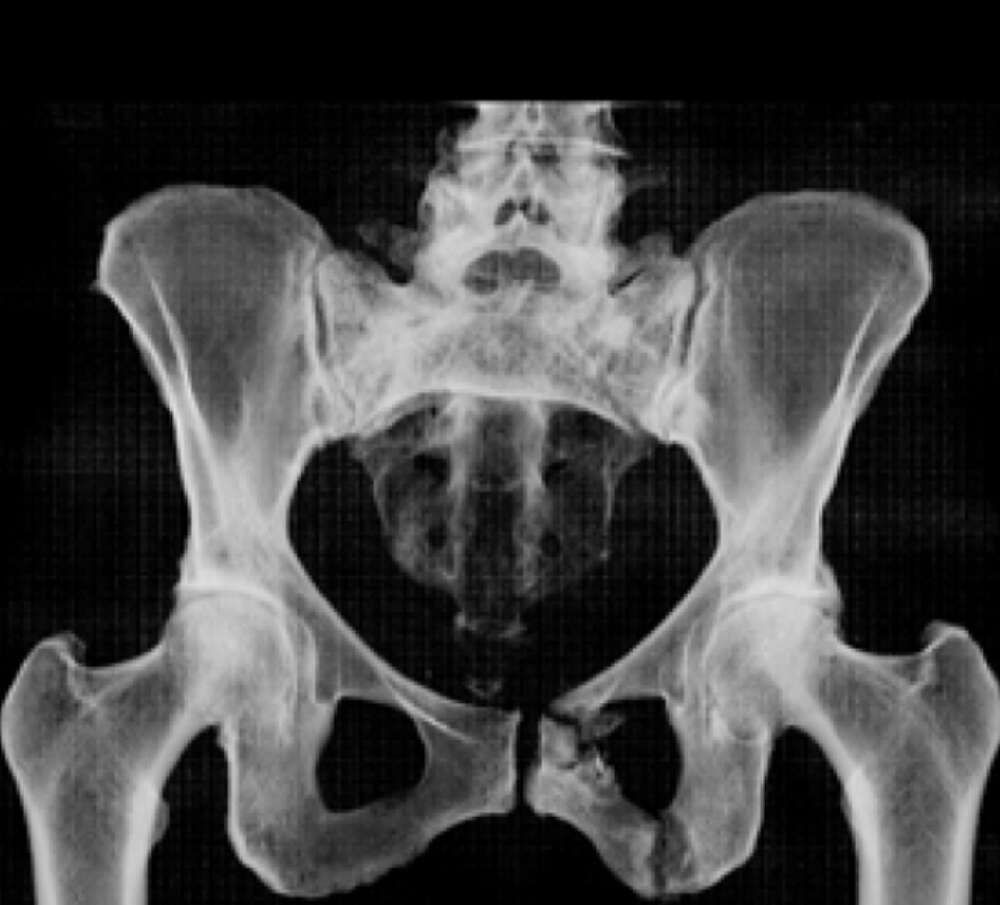

Lumbopelvic Instability after Chronic Sacral U- Fracture

Patient History:

• Fall 3 months prior

• Managed non-operatively by outside hospital

• 10/10 pain; difficulty ambulating x 3 mo

• MRI done and self-referral to IR for sacroplasty

• Referred to ortho by IR for pelvic fixation

Diagnosis:

• Chronic Sacral U-type fracture with kyphotic deformity

• Anterior ring disruption

• Osteopenia